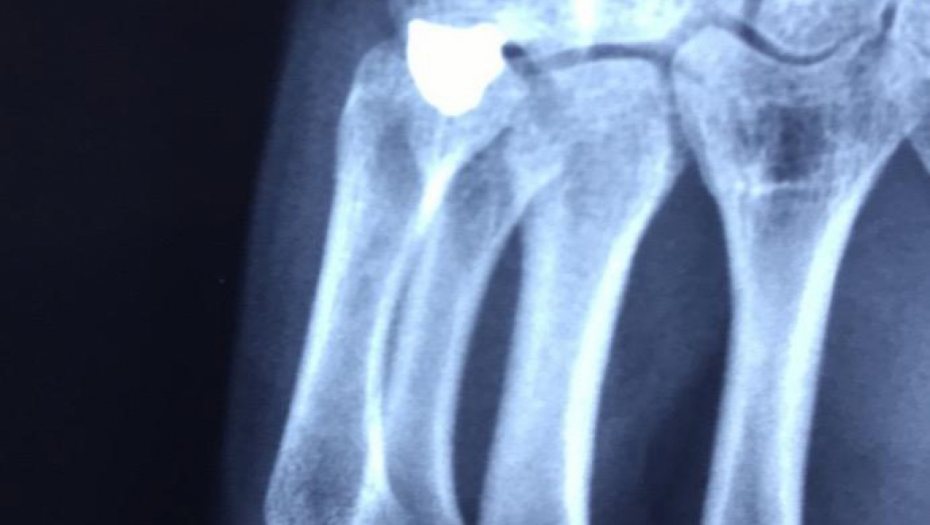

OBJAVLJEN RENDGENSKI SNIMAK Ovo je metak koji je izvađen iz šake srpskog mladića (FOTO)

U KBC Gračanica Miloš S. (21) izvađen metak koji je bio u šaci.

Ovde možete pogledati i rendgenske sinimke šake ranjenog mladića.